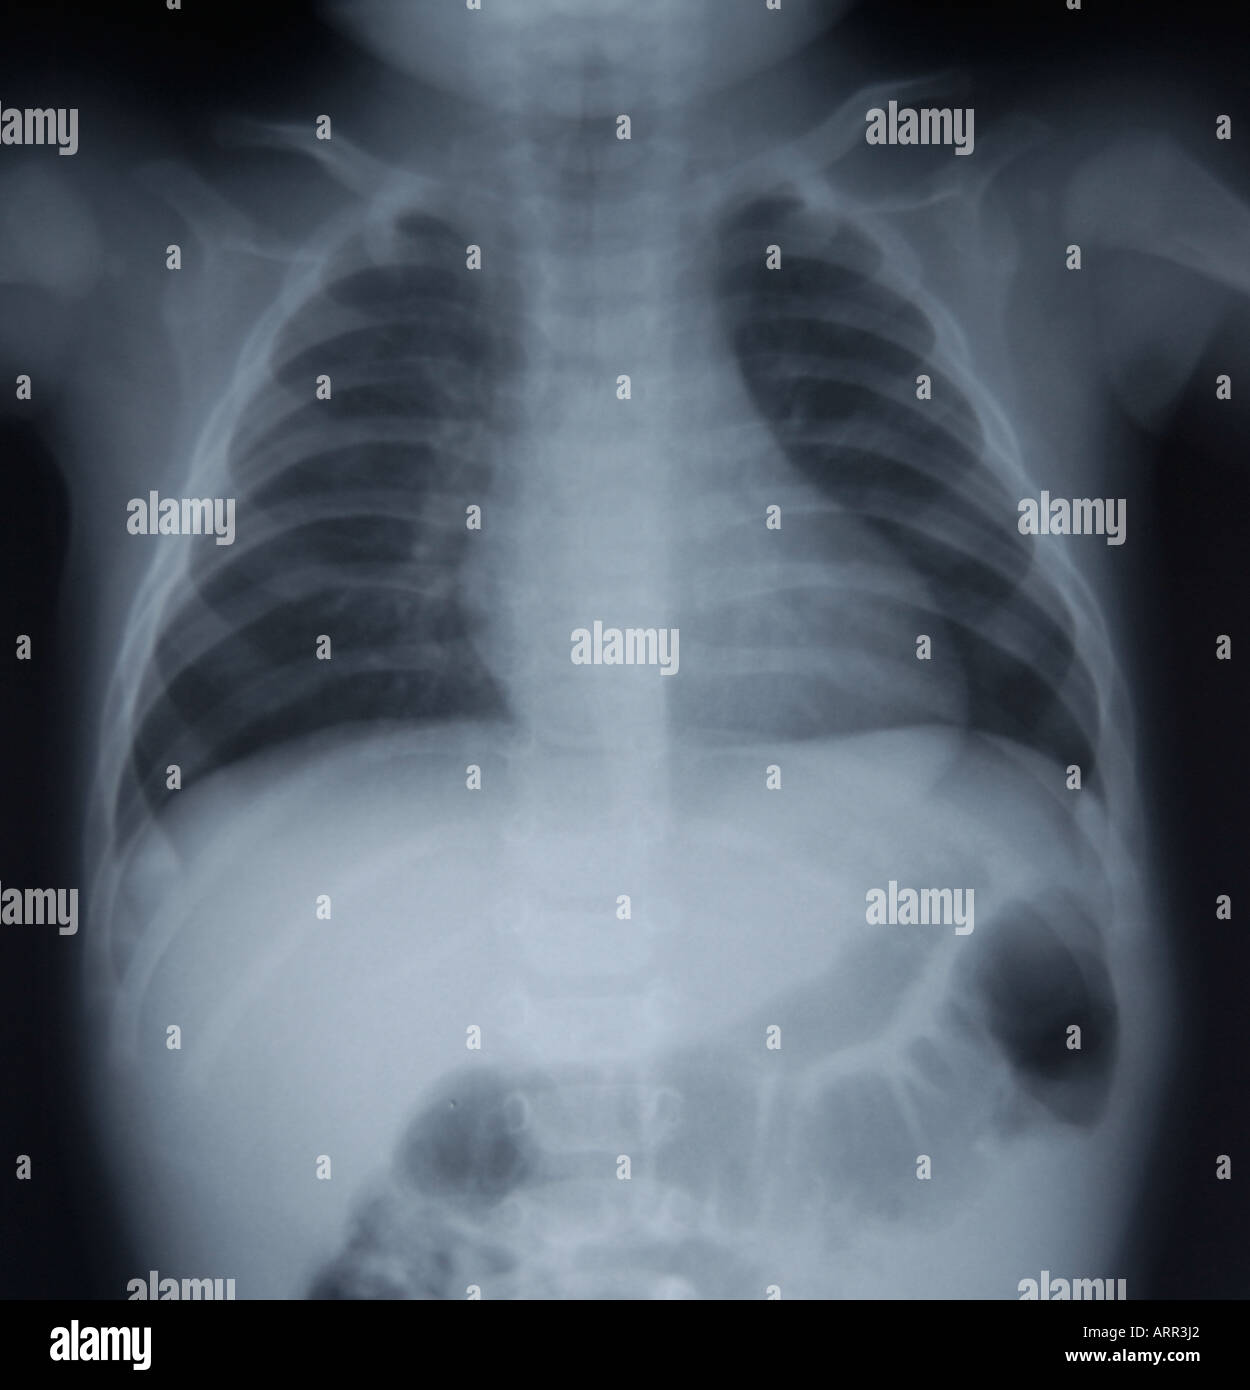

frontal view of normal pediatric chest xray Stock Photo Alamy